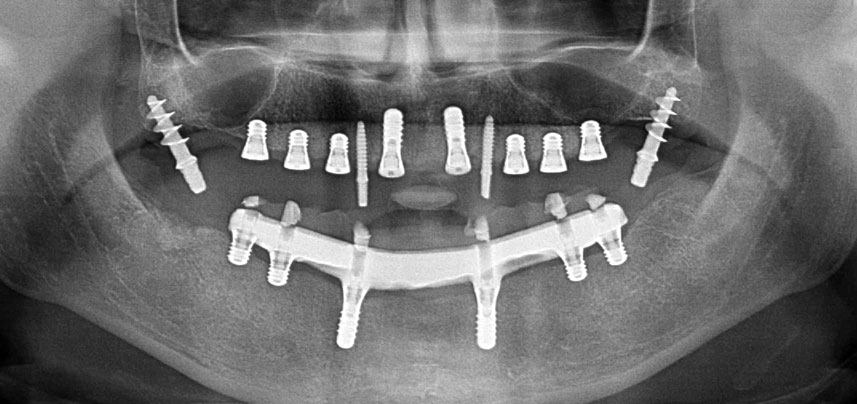

Due to the relatively hard bone (D2) in this area, the 10 mm long implant sites at positions 11 and 21 were finalized with a 4 mm diameter rotary drill, in combination with a W&H WS-75 L surgical contra-angle handpiece, the W&H Implantmed implant motor and the optional W&H Osstell ISQ module. In contrast, due to the soft bone the posterior sites were prepared to a final 3 mm diameter using the Piezomed I3P instrument. The implants were finally placed transgingivally to osseointegrate for three months (Figs. 6-10). The existing denture was retained on four provisional implants (Fig. 8).

Implant stability

Fig. 7: Implant stability is determined with a SmartPeg and the W&H Osstell ISQ module. All values are in the medium to high range, with a minimum of ISQ 69.

Post-operative panoramic radiograph

Fig. 10: The post-operative panoramic radiograph shows all implants in appropriate positions, including the pterygoid provisional implants.